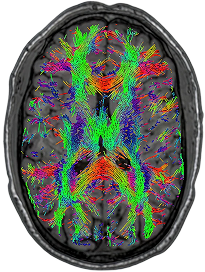

DTI - Tractography

0.5T

3 x 3 x 3mm

10:25

Images from: Halder et al., Investigating the feasibility of resting state functional MRI with GRE EPI on a high performance 0.5 T Scanner, processed using GraphICA, an asset of Brainet-Brain Imaging Solutions Inc.